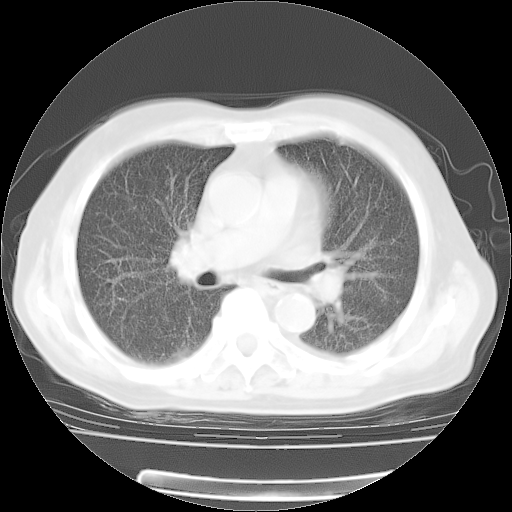

4月28日肺部CT——再次出现类似去年5月9日——磨玻璃样、间有“粟粒样”改变。